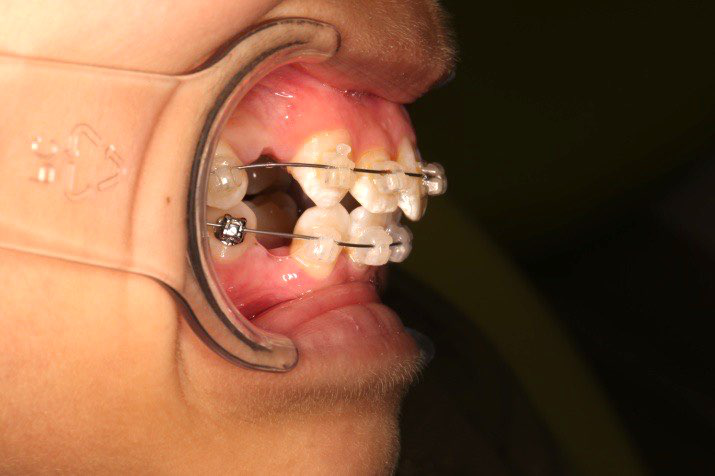

1.第0个月:2016.10.31 ◆ 初戴,0.013cu-niti

2.第2.5个月:2017.1.13 ◆ 上颌加TPA,植入1312-08种植钉,上下0.16cu-niti

3.第3.5个月:2017.02.16 ◆ 上下0.014*25 cu-niti,50g 尖牙远中

2016.10.31  初戴,0.013cu-niti2017.1.13  上颌加TPA,U56间斜形植入韩国庆北1312-08种植钉,上下0.16cu-niti

2017.02.16  上下0.014*25 cu-niti,50g 拉尖牙远中